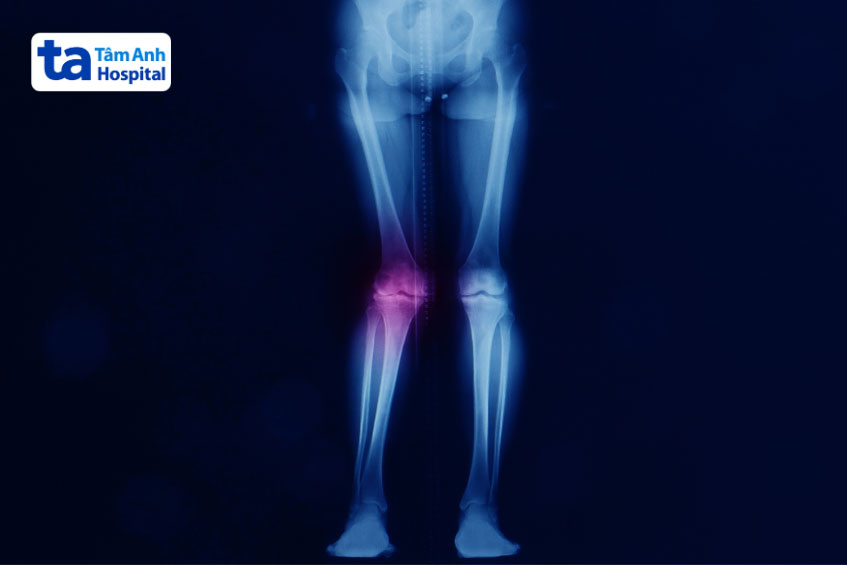

Chụp X-quang xương chân là một phương pháp quan trọng để đánh giá mức độ biến dạng của chân chữ X, bằng cách xác định góc giữa hông, gối và mắt cá chân. Bên cạnh đó, chụp X-quang cũng có thể phát hiện các nguyên nhân gây rủi ro cho xương như u xương, chấn thương hay còi xương…

Chụp X-quang để đánh giá mức độ biến dạng của chân chữ X ở người lớn